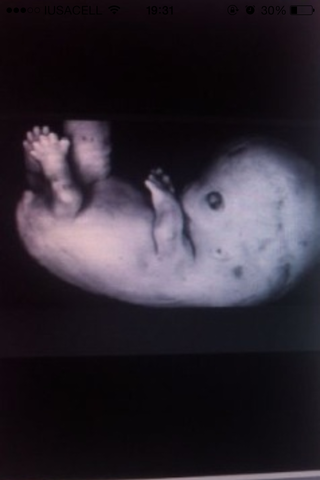

Se forma los parpados, labios superiores y nariz

Empiezan a formarse los brazos y piernas

Mide alrededor de 1.5 y 2 cm

Se van formando las costillas, rodillas, codos, brazos, piernas y dedos

Se forman las huellas digitales.